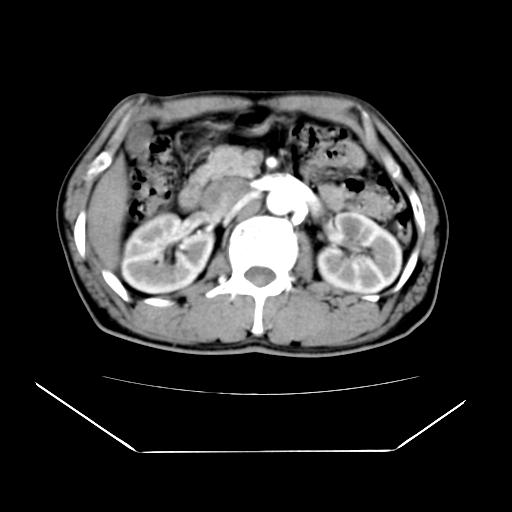

男性,55岁,外院体检afp明显升高,但b超未发现异常,否认乙肝病史。来我院ct增强。有延时扫描。

左肾囊肿.右肺中叶内侧段钙化灶.慢性胆囊炎.

肝脏右叶动脉期可见低密度影,至延迟期被充填,考虑血管瘤可能性大。

肝右叶病灶

不排除肝右叶肝癌可能。

如果这个是癌灶的话则下腔静脉有瘤栓可能

肝6段血管瘤

血管瘤可能性大。

考虑肝右静脉影。